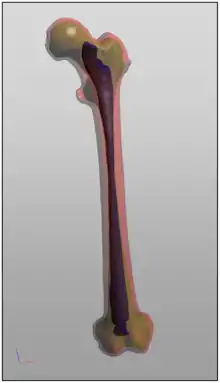

The result of image segmentation is a set of segments that collectively cover the entire image, or a set of contours extracted from the image (see edge detection). Each of the pixels in a region are similar with respect to some characteristic or computed property,[3] such as color, intensity, or texture. Adjacent regions are significantly different color respect to the same characteristic(s).[1] When applied to a stack of images, typical in medical imaging, the resulting contours after image segmentation can be used to create 3D reconstructions with the help of geometry reconstruction algorithms like marching cubes.[4]

- Medical imaging,[6][7] and imaging studies in biomedical research, including volume rendered images from computed tomography, magnetic resonance imaging, as well as volume electron microscopy techniques such as FIB-SEM.[8]